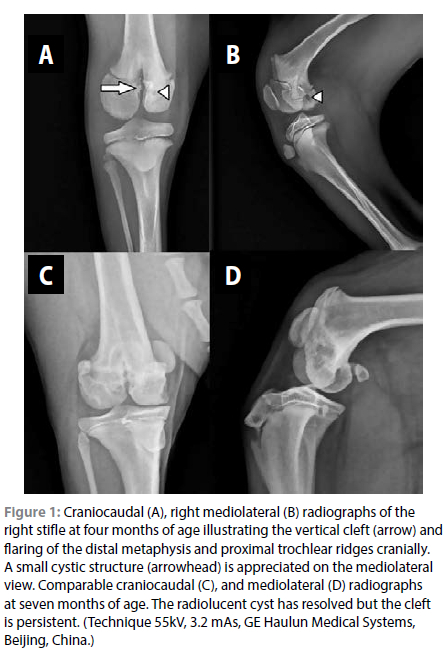

Repeat orthogonal mediolateral and craniocaudal radiographs of the left and right stifle were obtained under sedation to be compared to those obtained initially at four months of age. (55 kV and 3.2 mAs, GE Haulun Medical Systems, Beijing, China) (Figure 1).

These revealed a persistent radiolucent vertical cleft between the femoral condyles of the right limb, resulting in complete separation of the condyles from each other with the absence of bone and extension of the fissure through the distal physis into the distal femoral metaphysis. There was mild sclerosis of the margins of the cleft within the metaphysis, which had shown some progression. The subchondral bone of the lateral femoral condyle was rounder than it should be when compared to the normal opposite limb. The subchondral bone was also mildly irregular, with a small cystic structure of the medial condyle seen on the initial radiographs but with resolution in the follow-up study. The distal femoral metaphysis was flared cranially, resulting in a triangular cranial projection of the metaphysis proximal to the physis, which was normal, with a flattening of the trochlear ridges. No stifle effusion was noted. The right femur was approximately 8 mm shorter than the left (on approximation, with differences in limb positioning). The proximal tibial physis and apophysis were comparable to the opposite normal limb.